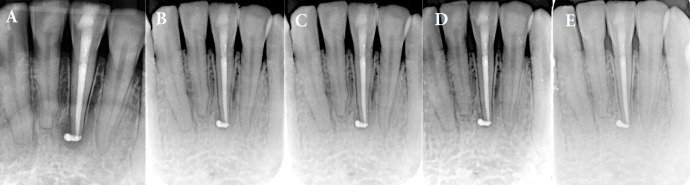

根管阻塞是由硬组织附着引起的,通常与有外伤史的牙齿、正畸运动、龋齿反应、靠近牙髓腔的修复手术以及老年患者的牙齿有关。根管治疗的术前规划应彻底,除辅助检查评估外,还包括对患者体征和症状的评估。一名 27 岁的患者患有下中切牙色素沉着症,有牙科外伤史,对垂直叩击有阳性反应,初次根尖周炎 X 光片显示根管钙化和根尖周炎病变。患者表现为咀嚼时疼痛,触诊和垂直叩诊试验均呈阳性反应。诊断结果为无症状根尖牙周炎。患者要求进行锥形束计算机断层扫描,并进行了表面扫描以建立静态导向。通过微创方法从牙根的中间三分之一处进入根管,并找到了根管位置。根管治疗采用传统方法。结果显示,经过 3 年的临床和放射学随访,治疗取得了成功。因此,在钙化根管病例中使用根管治疗引导器可以大大减少临床医生的工作时间,并为这些病变的治疗提供了一种更可预测的方法。

Root canal obliteration is caused by hard tissue apposition and is often associated with teeth with a history of trauma, orthodontic movement, caries reaction, restorative procedures near the pulp chamber, and teeth of elderly patients. Preoperative planning of root canal treatment should be thorough and include an assessment of the patient's signs and symptoms in addition to the evaluation of complementary examinations. In a 27-year-old patient with dyschromia of the lower central incisor, a history of dental trauma, and a positive response to vertical percussion, an initial periapical radiograph was obtained that showed calcification of the canal and presence of a periapical lesion. The patient presented with pain on chewing, a positive response to palpation and a vertical percussion test. The diagnosis was symptomatic apical periodontitis. A cone-beam computed tomography scan was requested and a surface scan was performed to establish a static guide. The root canal was accessed in the middle third of the root and the canal was located using a minimally invasive approach. The root canal was treated conventionally. Results obtained showed the success of the treatment after a 3-year clinical and radiographic follow-up. Therefore, the use of an endodontic guide in cases of calcified canals significantly reduces the clinician's working time and offers a more predictable approach to the treatment of these pathologies.